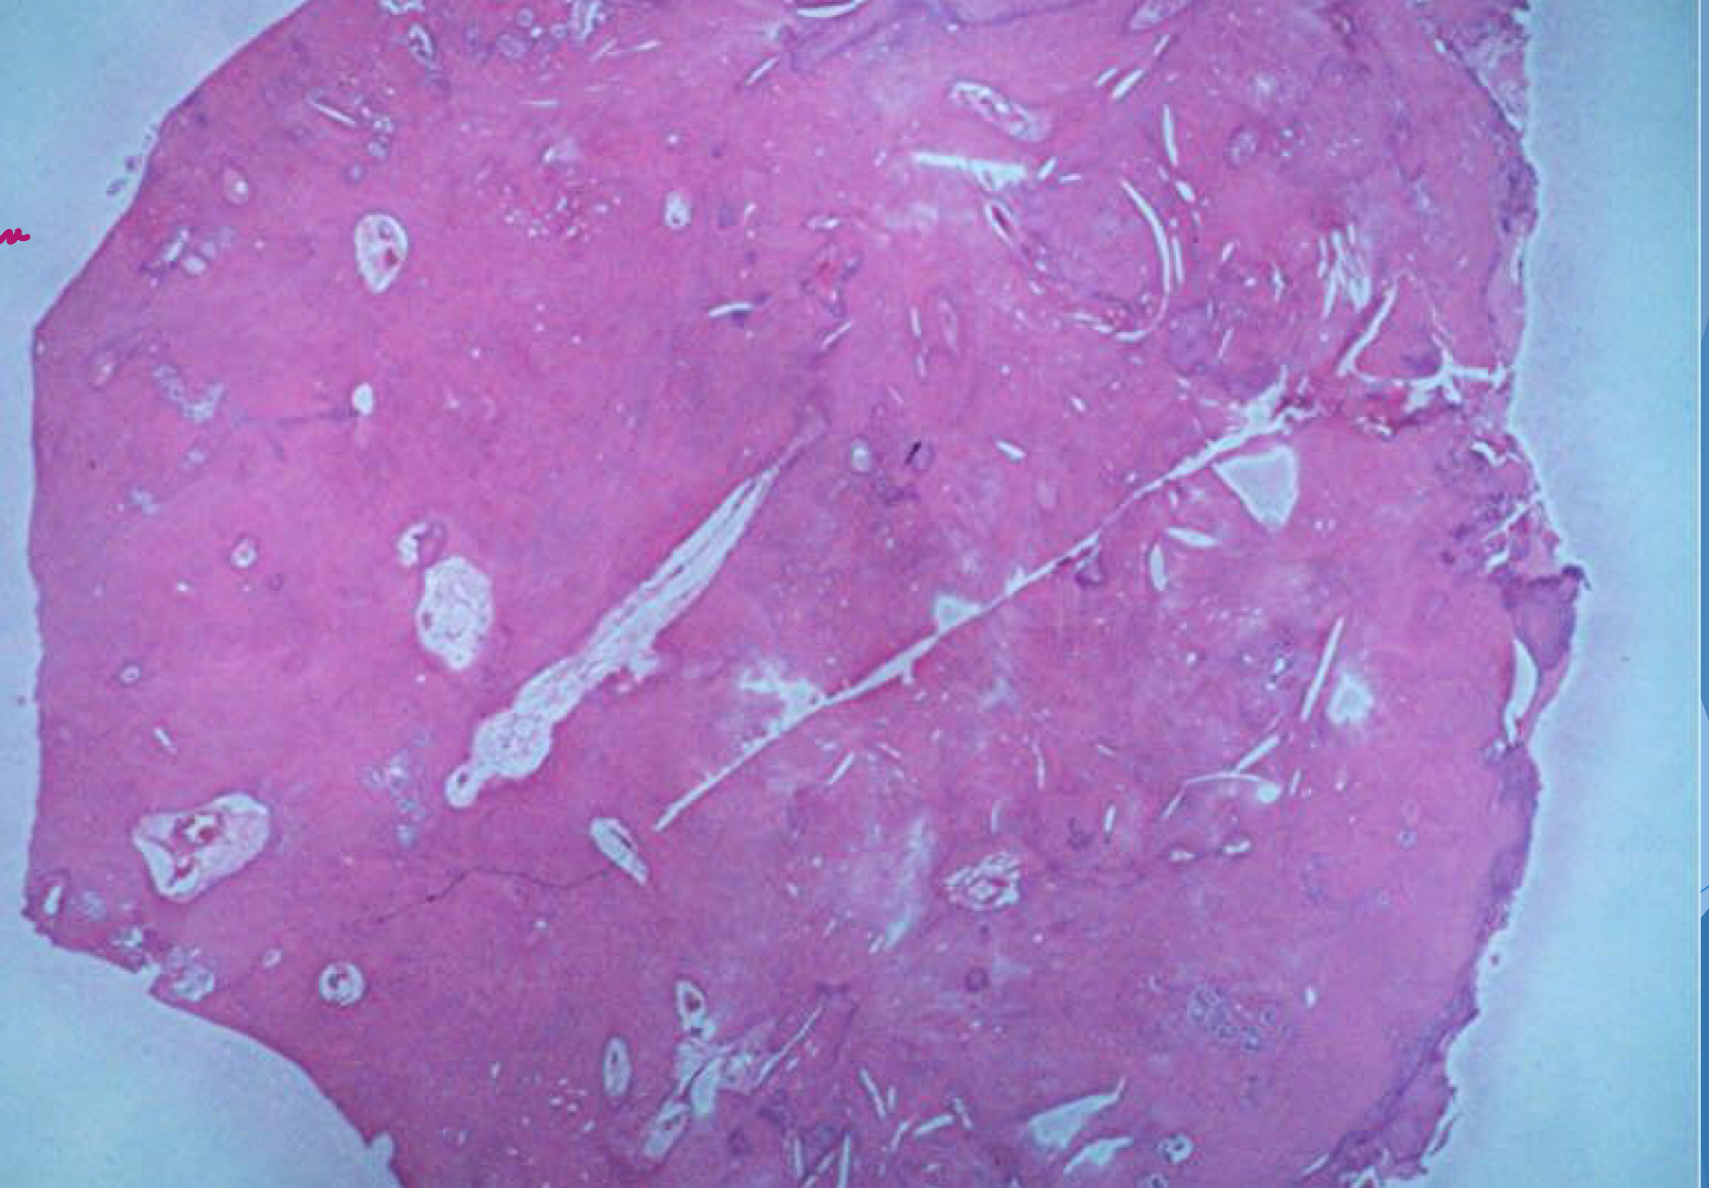

sclerotic bone = mineralized tissue vs granular tissue - less dense

condensing osteitis

which potential result of periapical inflammation?

treatment:Â

endodontic therapy or extraction of offending tooth

85% of cases will resolve or regress

bone scar may result following resolution of inflammation